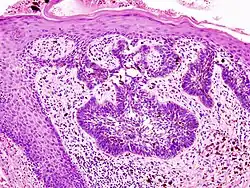

-

Basal cell carcinoma of the skin, cell nuclei (blue-purple), extracellular material (pink)